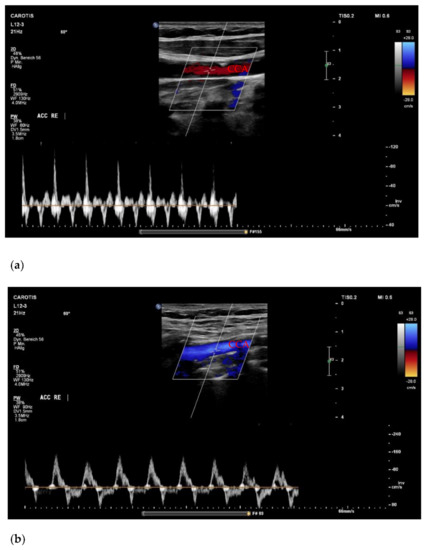

Figure 1. (a) Forward flow during compression/reverse flow during decompression in the CCA paired with small systolic peaks during conventional CPR; (b) Forward flow during compression/reverse flow during decompression with regular systolic peaks in a patient with transcatheter valve implantation. CCA = common carotid artery; CPR = cardiopulmonary resuscitation.

Utilizable US images were acquired in 14 cases (88%), and we completed the full imaging protocol in 11 patients (69%). Of those, five (63%) were measured during conventional CPR, four (25%) immediately after ROSC, and two (12%) during ECPR. All patients with incomplete imaging protocols were assessed during conventional CPR. There were no significant differences in peak systolic velocity (PSV) or enddiastolic velocity (EDV) between CPR, ECPR and ROSC cases. However, a trend towards higher values of EDV during ECPR could be shown (Table 1). In the comparison of flow velocities, only participants with completed imaging protocols were included. Concerning potential findings of clinical value, we detected a forward-flow during compression with a reverse flow during decompression in two cases (Figure 1) and a collapse of the CCA in one case (Figure 2). Videos of images of interest can be found in the Supplemental Material.

4.1. Dynamics in Carotid Artery Flow

The noted forward flow during compression with reverse flow during decompression (Figure 1) has been previously observed using a non-imaging probe in a porcine CA model [12]. A similar pattern is associated with the diagnosis of cerebral circulatory arrest, for which an internal carotid ultrasound is commonly used and a highly reliable procedure [13]. However, this biphasic flow can also be present in the CCA, which was chosen as the imaging site in our study [14]. The therefore hypothesized cerebral circulatory arrest could be caused by early cerebral edema, further decreasing the cerebral perfusion pressure during CPR [15] and could be seen as a general sign of cerebral injury. In line with this, both images in Figure 1 were acquired from patients with prolonged low flow times prior to admission, in one case preceded by a long no-flow time. However, since the images were acquired from the CCA, it is possible that the PW doppler flow signal was altered by the vessels connected to the external carotid artery that are—as peripheral vessels—responsive to vasopressors and therefore “biased” in terms of wall tension and blood flow in a hyperadrenergic state [16] for instance occurring after the administration of high-dose adrenaline. In addition, one of the two patients had previously undergone a transcatheter aortic valve implantation (TAVI). Aortic valve insufficiency is a common occurrence after TAVI, and CPR is a known factor potentially leading to an implant failure [17,18]. This is of relevance since aortic valve insufficiency can produce a PW doppler signal similar to our findings [14]. If our results, however, reflect a certain degree or state of cerebral perfusion during CPR, the PW doppler signal and especially the EDV—preferably measured in the internal carotid artery—might be of future diagnostic and prognostic value. Naturally, further research is required to draw adequate conclusions.